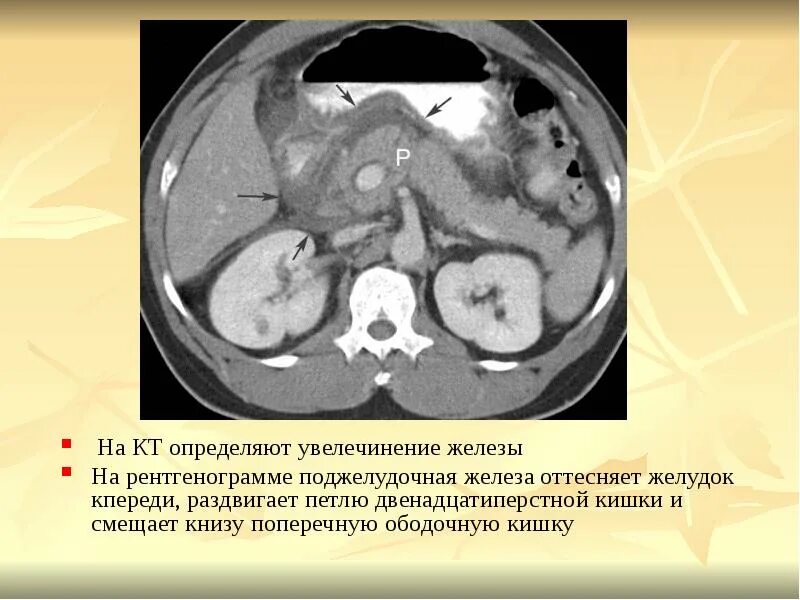

Инфильтрация паранефральной клетчатки на кт. параколитическая клетчатка кт. парапанкреатическая клетчатка инфильтрирована. перипанкреатический инфильтрат.Кт при остром панкреатите. парапанкреатическая клетчатка. кт диагностика панкреатита. острый отечный панкреатит кт.Парапанкреатическая клетчатка. поддиафрагмальное пространство. внебрюшинное поддиафрагмальное пространство. парапанкреатическая клетчатка инфильтрирована.Парапанкреатическая клетчатка что это значитКлетчатка анатомия. понятие о клетчатке в анатомии. основы клинической анатомии. клетчатка понятие.Парапанкреатическая клетчатка что это значитПарапанкреатическая клетчатка. парапанкреатическая клетчатка инфильтрирована. парапанкреатическая инфильтрация. парапанкреатическая клетчатка дифференцирована.Парапанкреатическая клетчатка что это значитПарапанкреатическая клетчатка что это значитХронический панкреатит на кт. парапанкреатическая клетчатка на кт. кт поджелудочной железы. поджелудочная железа на рентгенограмме.Парапанкреатическая клетчатка что это значитПарапанкреатическая клетчатка что это значитПарапанкреатический инфильтрат. парапанкреатическая клетчатка дифференцирована.Парапанкреатическая клетчатка что это значитПарапанкреатическая клетчатка что это значитПарапанкреатическая клетчатка поджелудочной железы. отек парапанкреатической клетчатки. парапанкреатическая инфильтрация. острый деструктивный панкреатит кт.Парапанкреатическая клетчатка что это значитПарапанкреатическая клетчатка что это значитПарапанкреатическая клетчатка что это значитПарапанкреатическая клетчатка что это значитПарапанкреатическая клетчатка что это значитПарапанкреатический инфильтрат. перипанкреатический инфильтрат. парапанкреатическая псевдокиста на кт.Парапанкреатическая клетчатка что это значитПарапанкреатическая клетчатка что это значитПарапанкреатическая клетчатка что это значитПарапанкреатическая клетчатка что это значитПарапанкреатическая клетчатка что это значитПарапанкреатическая клетчатка что это значитПарапанкреатическая клетчатка что это значитПарапанкреатическая клетчатка что это значитПарапанкреатическая клетчатка что это значитПарапанкреатическая клетчатка поджелудочной железы. перипанкреатический инфильтрат. осложнения острого панкреатита презентация. перипанкреатическая клетчатка.Парапанкреатическая клетчатка что это значитКисты и свищи поджелудочной железы. инфильтрация парапанкреатической клетчатки. истинные кисты поджелудочной железы классификация. парапанкреатическая клетчатка поджелудочной железы.Парапанкреатическая клетчатка что это значитПарапанкреатическая клетчатка что это значитПарапанкреатическая клетчатка что это значитПарапанкреатическая клетчатка что это значитПарапанкреатическая клетчатка что это значитПарапанкреатическая клетчатка что это значит